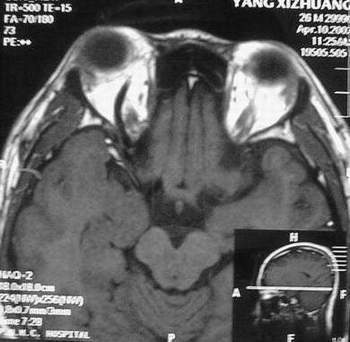

MRI及增强结果如下:

患者压颈及其它Valsava试验结果阴性。从MRI分析,在T1、T2、T+C检查该支血管均为明显流空现象,说明该血管血流速度很快,而从走行和分布看,眼上静脉可能性很大。也许也不能除外异常的眼动脉或异常血管。眶内主要可能的血管病变包括颈内动脉海绵窦瘘(高流窦)、AVM、眼眶静脉曲张、海绵状血管瘤、静脉性血管瘤、毛细血管瘤和眶内动脉瘤。。

1、颈内动脉海绵窦瘘:该患者临床有一部分支持该诊断。但从影像分析,海绵窦未见明显扩张;眼外肌未见明显充血扩张的长T1、长T2信号;颈内动脉海绵窦瘘常可见继发到血栓,可见到短T1、长T2的血栓信号。

2、眼眶静脉曲张:该疾患一般常见于小儿。该患大多数会出现Valsava试验阳性,间歇性突眼。不符合该患。影像学检查,于曲张静脉内常可见血栓和静脉石。所以不符合该患。

3、AVM:患者目前的影像学资料尚不全面,但可符合该诊断。临床上改病常见于30岁左右年轻人,单侧发病,于本患较符合。问题在于临床没有明确的血管杂音,似乎难以解释。

4、该患影像学与海绵状血管瘤差别很大,所以可基本排除此诊断。

5、静脉性血管瘤和毛细血管瘤:MRI中等T1、长T2信号,较易与本病鉴别。

6、眶内动脉瘤:我觉得患者并不能排除本病,但同样,由于波动性阴性,似乎也难以解释。

纵上所述:本人觉得,患者AVM可能性较大,同时不能除外眶内动脉瘤。